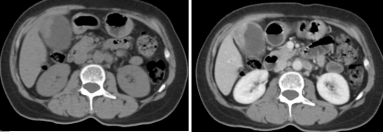

1腺炎CT表现:多数有胰腺弥漫性增大,少数轻者表现正常;密度正常或略减低,均匀或不均匀;胰腺轮廓清楚或模糊,渗出明显者可有胰周积液;肾前筋膜及肾周筋膜增厚;增强扫描胰腺均匀强化。

肾旁前间隙、肾后间隙积液

腺炎MRI表现:胰腺局限/弥漫肿大,呈T1低信号、T2高信号;胰腺轮廓清楚或模糊,渗出明显者可有胰周 或胰外积液,呈T1低信号、T2高信号;合并出血,T1T2皆呈高信号;增强扫描:水肿型,胰腺均匀强化 ;坏死型,胰腺不均匀强化,坏死区无明显强化。